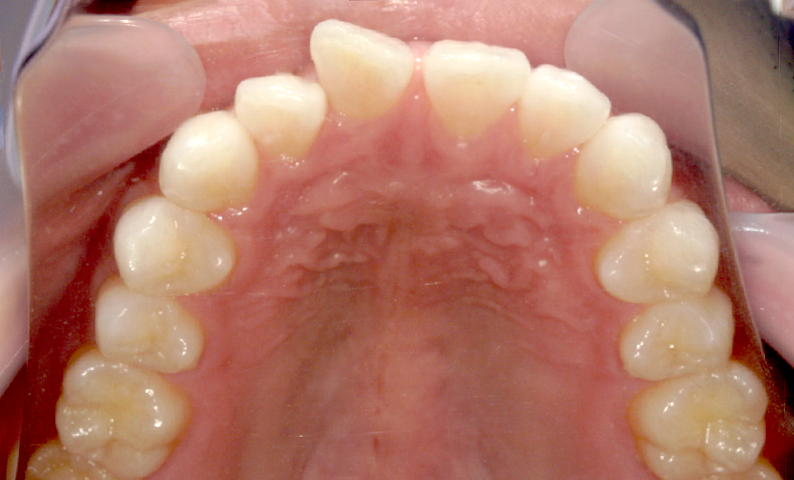

| 治療前 | 治療後 |

|---|---|

|